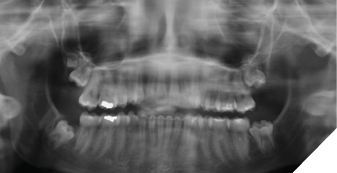

The patient was seen again one year later and deemed appropriate to proceed with surgery. Teeth #18, 28, 38 and 48 were removed under general anesthesia. Tooth #19 was retained due to its high position, and the patient remained in follow-up (Fig. 3).

Fig. 3